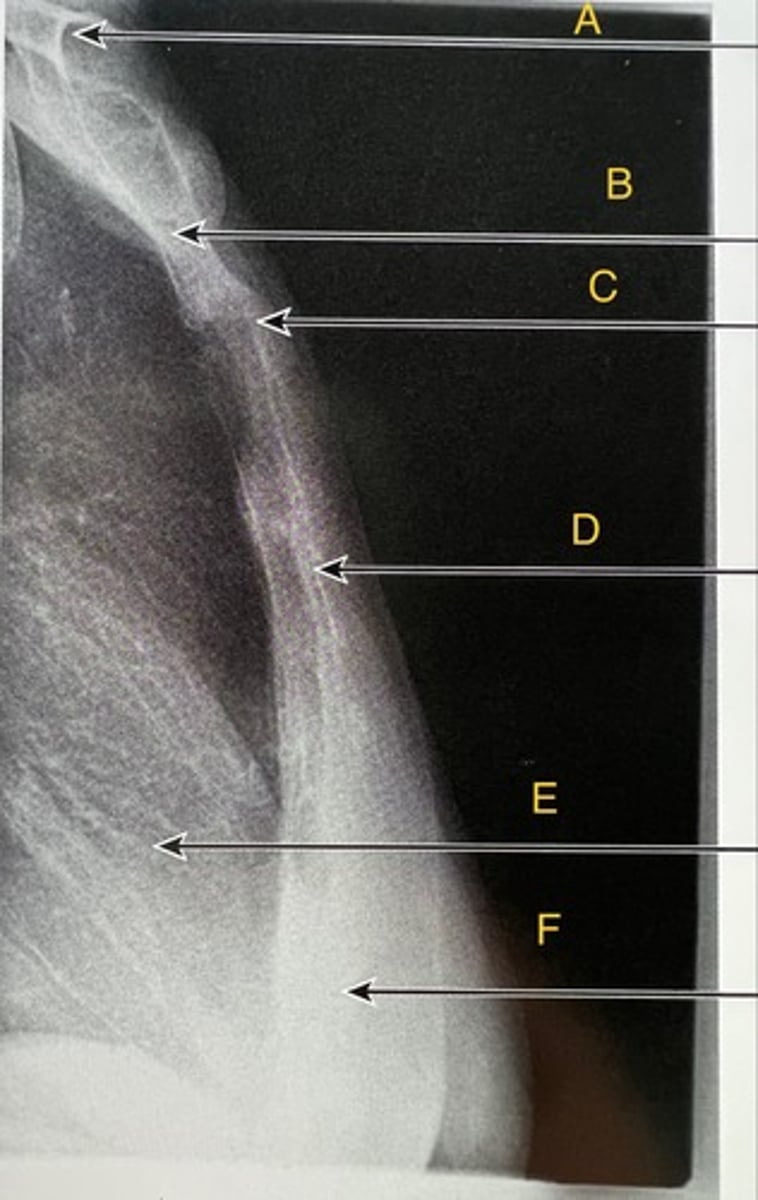

Clavicles

A.

Manubrium

B.

Sternal angle

C.

body of sternum

D.

Heart

E.

Xiphoid process

F.

Lateral sternum

What position?